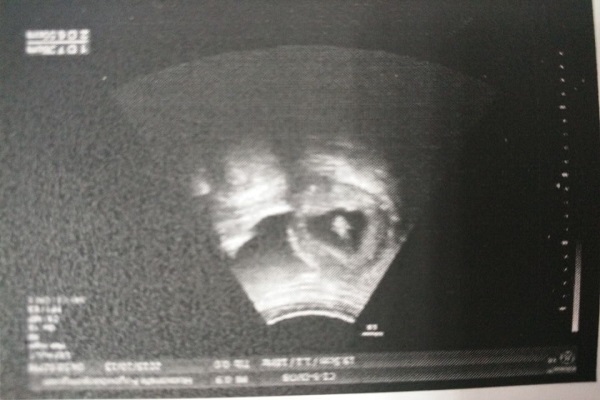

在5月初的时候,我与莎莎抱着忐忑的心情来到了医院,但是医生的回答却让莎莎心情跌入谷底。医生告诉莎莎通过B超和尿检的结果显示莎莎并没有怀孕。